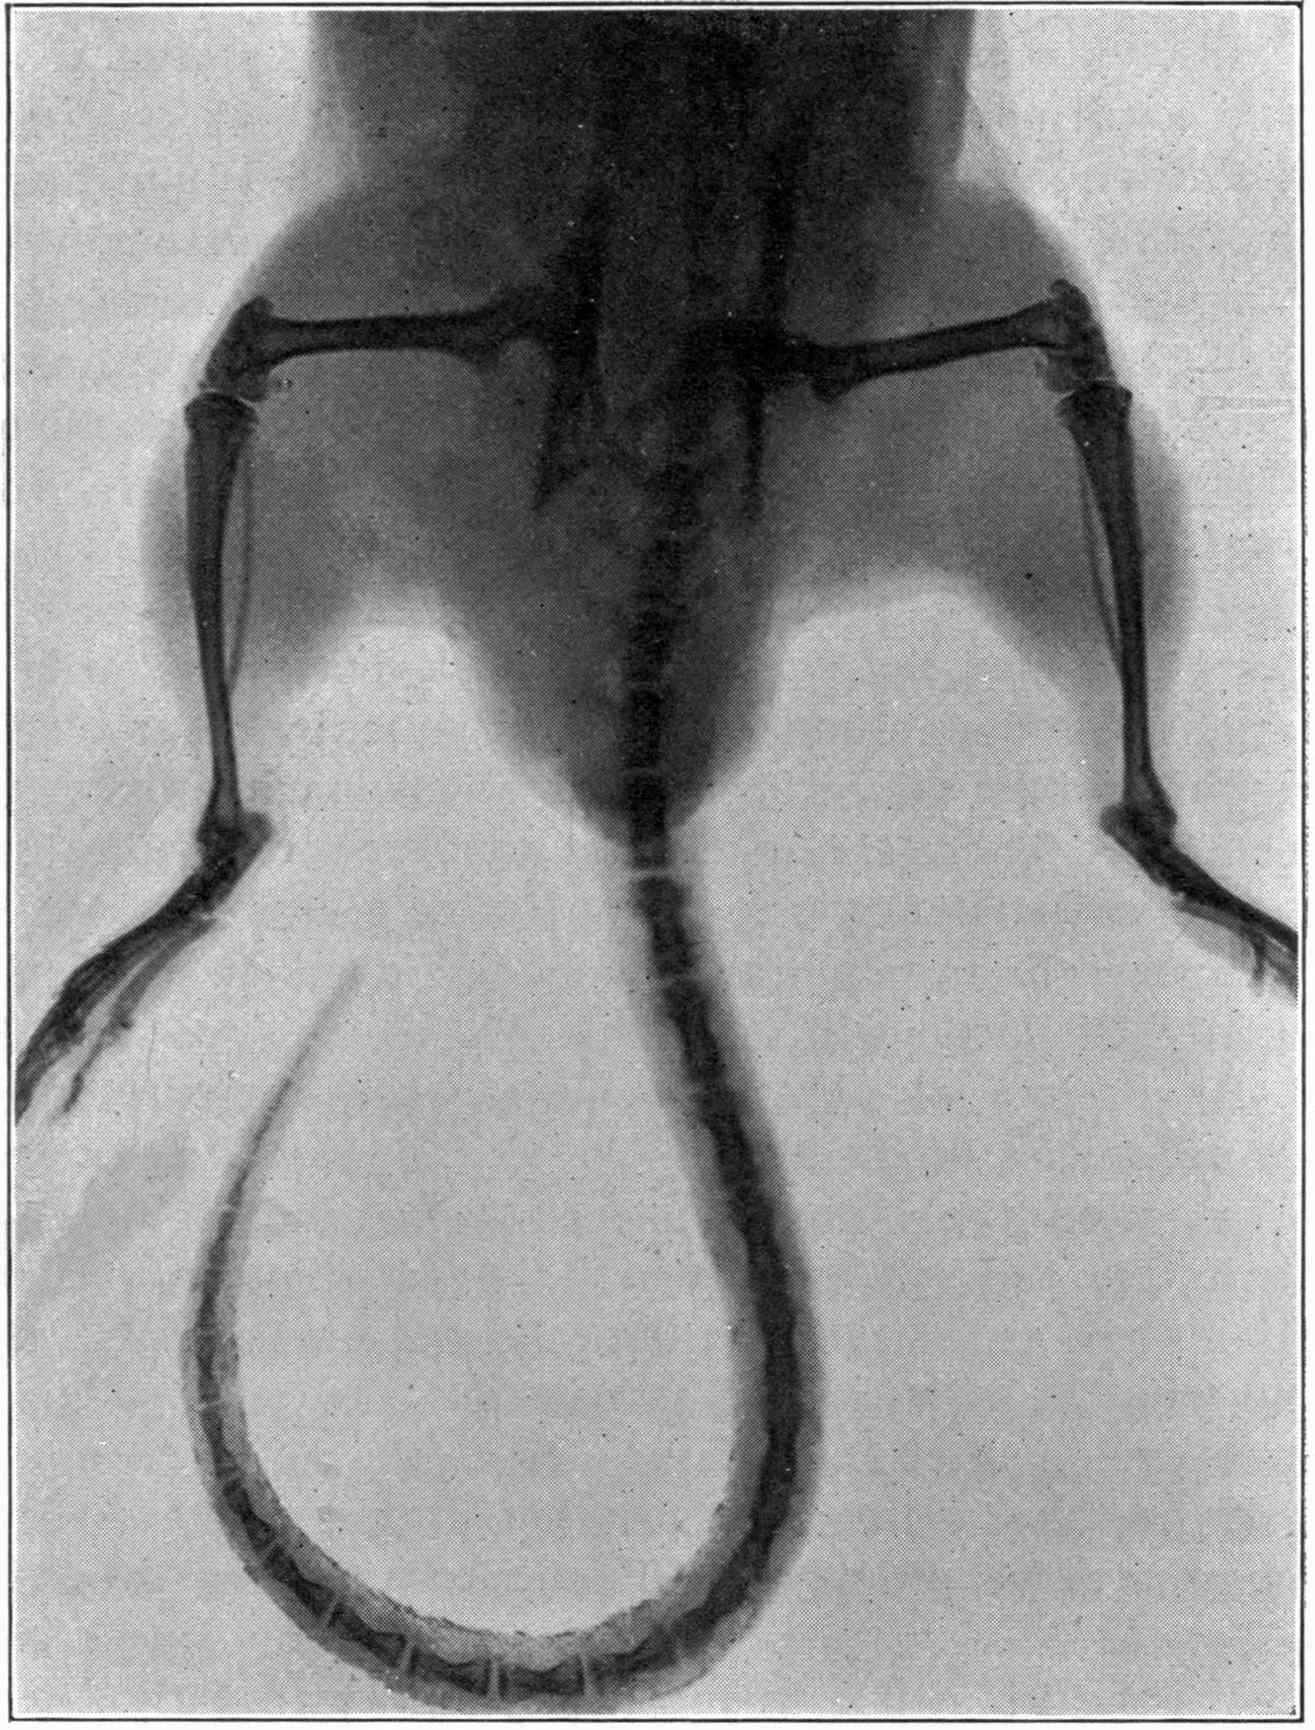

| 206. | Elements of the Thorax. | Morton |

| 207. | A Colles’ Fracture Detected by X-rays. | Morton |

| 208. | Motions of Liver, Outlines of Spleen, and Tuberculosis Indicated. | Morton and Williams |

| 209. | Osteomyelitis distinguished from Periostitis. | Lannelongue, Barthelemy, and Oudin. |

| 210. | Concluding Miscellaneous Experiments Relating to Similar Applications of X-rays. | Ashhurst, Packard, Müller, Keen, and Morton, T. G. |